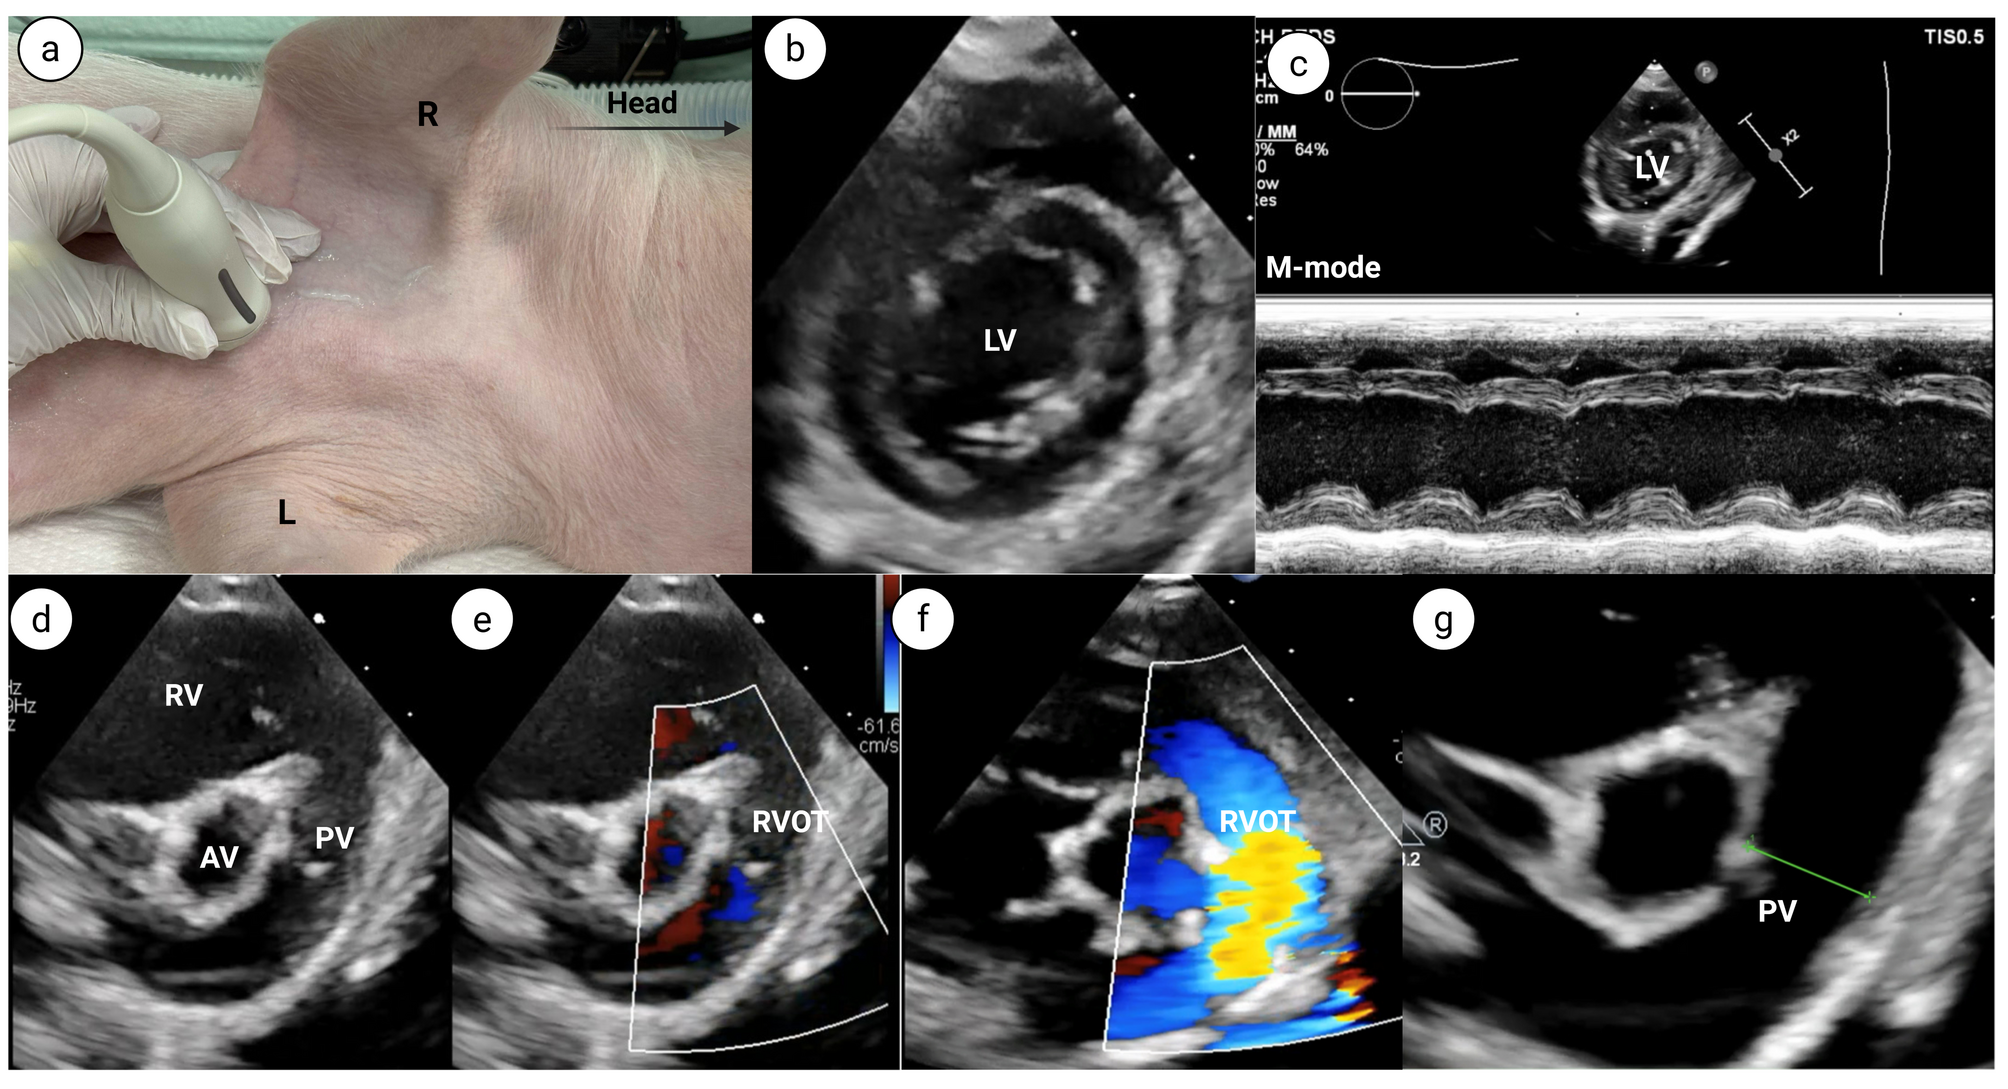

Fig. 3

From: Transthoracic echocardiography for evaluating cardiac parameters in growing piglets

Parasternal long axis (PLAX) view.